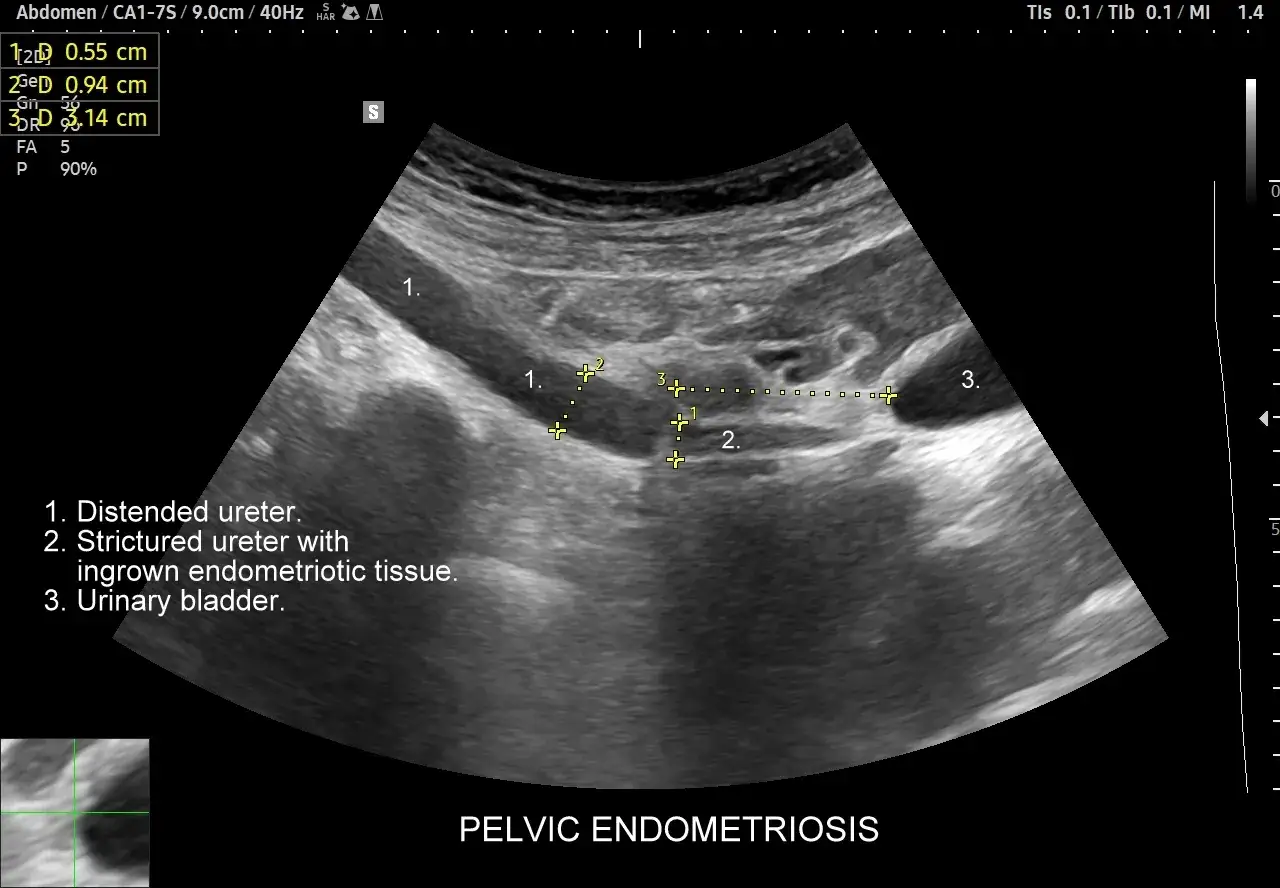

Po wstępnym wywiadzie i badaniu fizykalnym, lekarz często zleca badania obrazowe. Kluczowe w diagnostyce endometriozy jest specjalistyczne badanie ultrasonograficzne (USG), często wykonywane przez doświadczonego specjalistę, który potrafi ocenić narządy miednicy mniejszej z dużą dokładnością. Szczególnie cenne jest USG przezpochwowe z użyciem sondy o wysokiej częstotliwości, które pozwala na uwidocznienie ognisk endometriozy, torbieli endometrialnych (tzw. "torbieli czekoladowych") czy zrostów. W bardziej skomplikowanych przypadkach, gdy istnieje podejrzenie głębokiej endometriozy naciekającej na narządy jamy brzusznej, lekarz może zlecić rezonans magnetyczny (MRI), który daje jeszcze bardziej szczegółowy obraz tkanek.

- Stopień IV (ciężki): Choroba jest zaawansowana, z licznymi, głębokimi ogniskami, dużymi torbielami endometrialnymi na obu jajnikach, rozległymi zrostami, a czasem z naciekaniem innych narządów, np. jelit czy pęcherza moczowego.